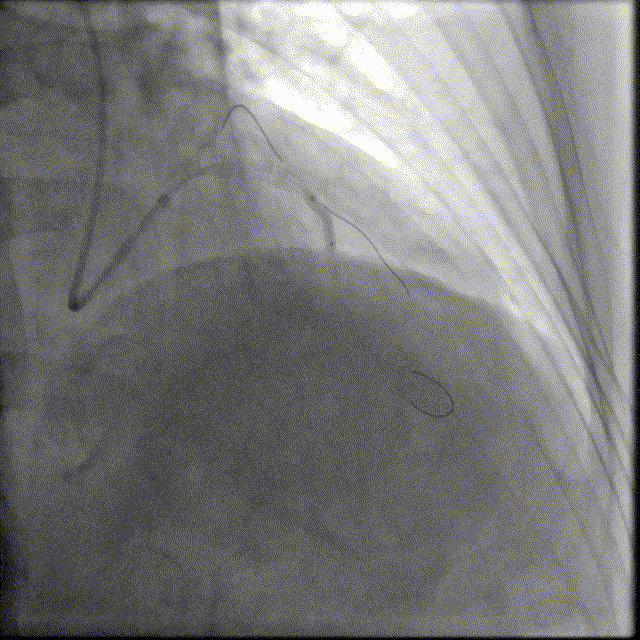

于前降支中段近段口串联2.5mm×18mm、3.0mm×18mm DES。

前降支开口精确定位植入3.5mm×18mm DES。

2.5mm-3.5mm后扩球囊后扩张。

最终结果满意,复查IVUS支架膨胀、贴壁良好!